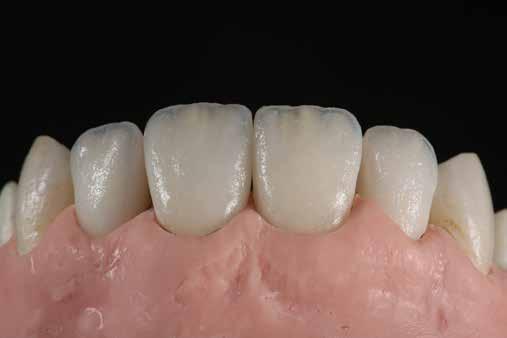

A szakirodalomban fellelhető eredmények alapján kerámia héjak ragasztására a kontaminációtól mentes, frissen vágott zománc felszín a legalkalmasabb. A hosszú távú sikeresség elérésének további feltétele a fogak konzervatív módon történő preparálása, továbbá a ragasztás kofferdám felhelyezésével biztosított, abszolút izolálásban történő kivitelezése. Úgy véljük, hogy a fenti faktorok biztosították a cikkben bemutatásra kerülő esetek – 5 évvel az átadás után megfigyelhető – sikerességét. A kofferdám izolálás alkalmazása számos előnyt biztosít a gyakorló fogorvos számára. Megakadályozza a munkaterület nyállal, vérrel, vagy szulkusz-váladékkal történő kontaminációját, és javítja a kezelendő területre való rálátásunkat. A fogak kerámia héjak ragasztása előtt történő izolálása azonban gyakran kihívást jelenthet a kevesebb klinikai tapasztalattal rendelkező fogorvosok számára. Jelen esetbemutatásban ismertetjük a kofferdám felhelyezésének lépéseit és néhány olyan gyakorlati tanácsot, amelyek jelentősen megkönnyíthetik a munkánkat, azokban az esetekben, amikor a második kisőrlőfogak közti területet kívánjuk kofferdám segítségével izolálni. A kofferdám kapcsok segítségével került rögzítésre, majd fogakat körülvevő széleit óvatosan az ínybarázdába forgattuk. A kerámia héjak számára előkészített fogakra ragasztás előtt egyenként kapcsokat helyeztünk annak érdekében, hogy a kerámia héjak rögzítése ideális körülmények között történhessen. A lépések részletes ismertetése segítséget jelenthet – a kevesebb klinikai tapasztalattal rendelkező fogorvosok számára – az abszolút izolálás megvalósításához szükséges lágyrészmenedzsment megértéséhez. Ezek az ismeretek rendkívül hasznosak lehetnek, ha a jövőben a kerámia héjak ragasztását megfelelő módon megvalósított kofferdám izolálás mellett kívánják kivitelezni. A cikkben ismertetett módszerek alkalmazásával az abszolút izolálás megvalósítható, a gumilepedő – vérzés nélkül – ínybarázdába történő beforgatására, és a ragasztáshoz szükséges idő csökkentésére.

Az előzetes állapotfelmérést és a kezelés megtervezését követően a fogakat minimál invazív módon preparáltuk (1. a-b ábrák), majd az előkészített fogak ínybarázdáiba fonalbehelyező eszköz segítségével (113 Serrated Gingival Cord Packer, Hu-Friedy, Chicago, Illinois) teflonszalagot helyeztünk (Loctite Thread Seal Tape, Henkel Loctite Corp., Egyesült Államok), (1. c ábra). A hagyományos retrakciós fonalak helyett, a rugalmasságuk miatt előnyösebbnek tartjuk a teflonszalagok használatát. A kofferdámot (Dental Dam, Nic Tone, Bukarest, Románia) az előkészített fogakon kívül, az azoktól disztálisan elhelyezkedő egy-egy fognak megfelelően is perforáltuk.

Az oxigén inhibíciós réteg kialakulásának elkerülése érdekében a kerámiafelszíneket glicerin géllel (Liquid Strip, Ivoclar Vivadent, Schaan, Liechtenstein) borítottuk, majd ezeket a felszíneket ismét 20-20 másodpercen keresztül világítottuk. A végeredmény megfelelt a páciens esztétikai igényeinek (6. a. ábra). Az átadott restaurátumok épségének megőrzése érdekében, a páciens számára éjszakai fogvédő sín készült. Az ötéves kontroll alkalmával megállapítottuk, hogy az elvégzett kezelésünk továbbra is sikeresnek tekinthető (6. b. ábra)

Az általunk alkalmazott adhezív rendszerek hatékonyságát nagymértékben növelhetjük azáltal, hogy a fogakat minimál invazív módon, azaz csak zománcon belül preparáljuk, és a kerámia héjakat kofferdám izolálásban ragasztjuk. Jelen esetismertetésünknek az volt a célja, hogy bemutassuk, hogyan lehet az adekvát módon kivitelezett kofferdám izolálással megelőzni

a munkaterület nyállal, vérrel vagy szulkusz-váladékkal történő kontaminációját. A megfelelő méretben kialakított perforációs nyílások és köztük lévő optimális távolság elengedhetetlen ahhoz, hogy a kofferdámot ideális módon tudjuk felhelyezni. Ezzel az esettel azt is bizonyítjuk, hogy a gumilepedő levegőfújással, fogselyemmel és teflonszalagok segítségével történő beforgatásával az ínyvérzés kialakulását el lehet kerülni. Ismételten szeretnénk hangsúlyozni, hogy a megfelelő kofferdám kapcsok használata nélkül nem tudtuk volna a preparált csonkszélt a gumilepedő szélétől eltartani. A kezelés során elért eredményeket jól alátámasztotta, hogy a páciens az ötéves kontroll vizsgálat során teljesen elégedett volt.